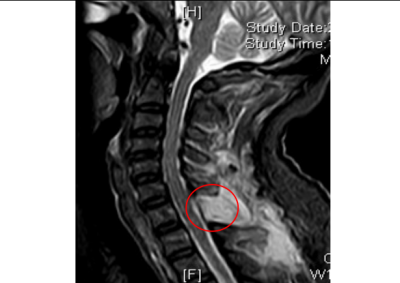

术后复查核磁检查,颈胸段椎管内肿瘤已切除干净